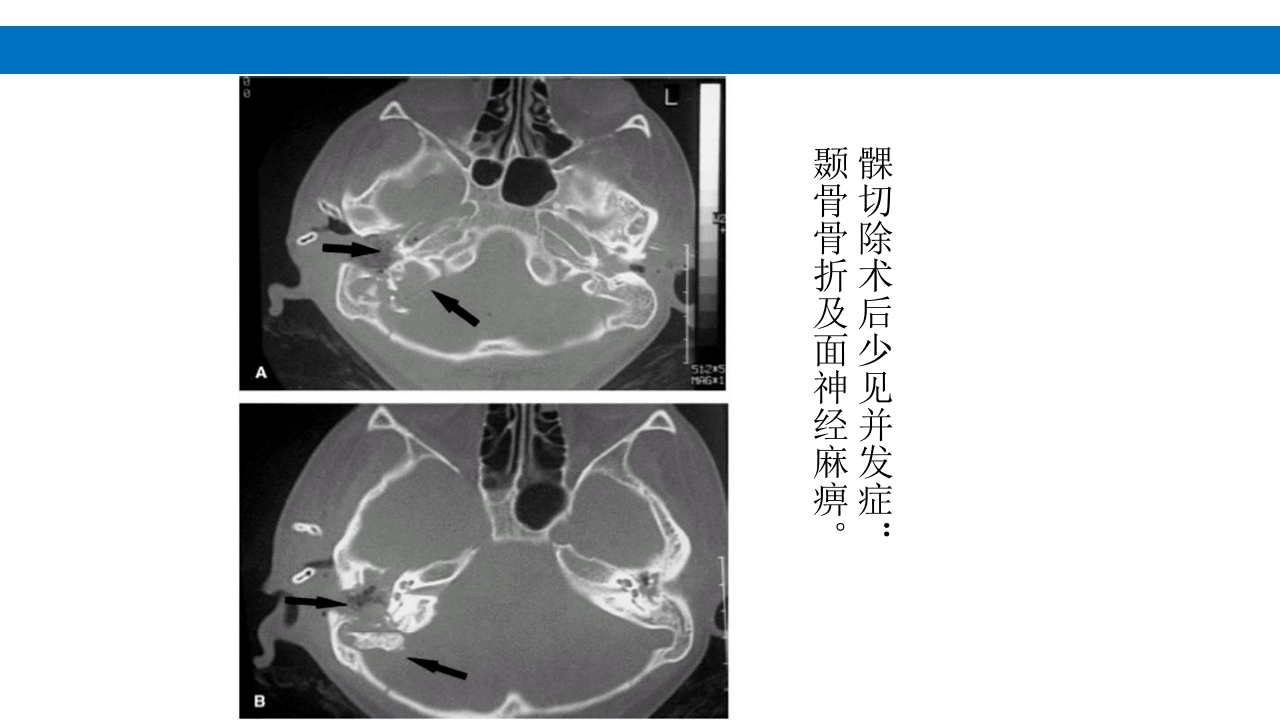

颅脑损伤的并发症及后遗症 讲解人:xxx 20XX年x月x日 1.颅骨骨髓炎 病因:为头皮软组织、中耳、乳突和副鼻窦等处炎性感染而经导 血管侵入颅骨内或颅脑开放伤感染所引起,亦可由菌血症后发生 的细菌栓子由血运转移至颅骨内。 影像学表现: 头部CT: 1.表现为不规则的蜂窝状骨质破坏区,主要位于板障,亦可累 及内外板。 2.破坏区内可见高密度的米粒状细小的高密度死骨。 3.周边可见骨质硬化增生,颅板外无骨膜反应。 4.局部的头皮可见软组织肿胀。 头部MRI: 由于受累部位细胞成分和水量增多,T1WI为低信号, T2WI为高信号,急性期边界不清,慢性期病灶局限, 边界清晰。MRI显示骨质破坏没有CT效果好。 治疗: 除应用抗菌药物控制感染外,当感染局限或已有死骨形成后, 应行手术切除感染...